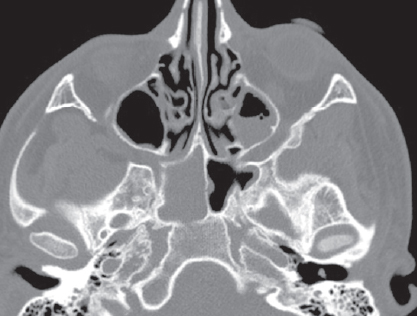

По результатам КТ ОНП от 08.11.2021: правосторонний сфеноидит с уровнем жидкости, левосторонний верхнечелюстной синусит с уровнем жидкости (рис. 4–6).

Рис. 4. Компьютерная томография околоносовых пазух и головного мозга от 08.11.2021: аксиальная проекция в режиме skull. Тотальное затенение правой половины пазухи клиновидной кости справа, уровень жидкости в левой верхнечелюстной пазухе

Fig. 4. Computed tomography of the paranasal sinuses and brain from 08.11.21: axial projection in skull mode. Total shading of the right half of the sphenoid sinus on the right, fluid level in the left maxillary sinus